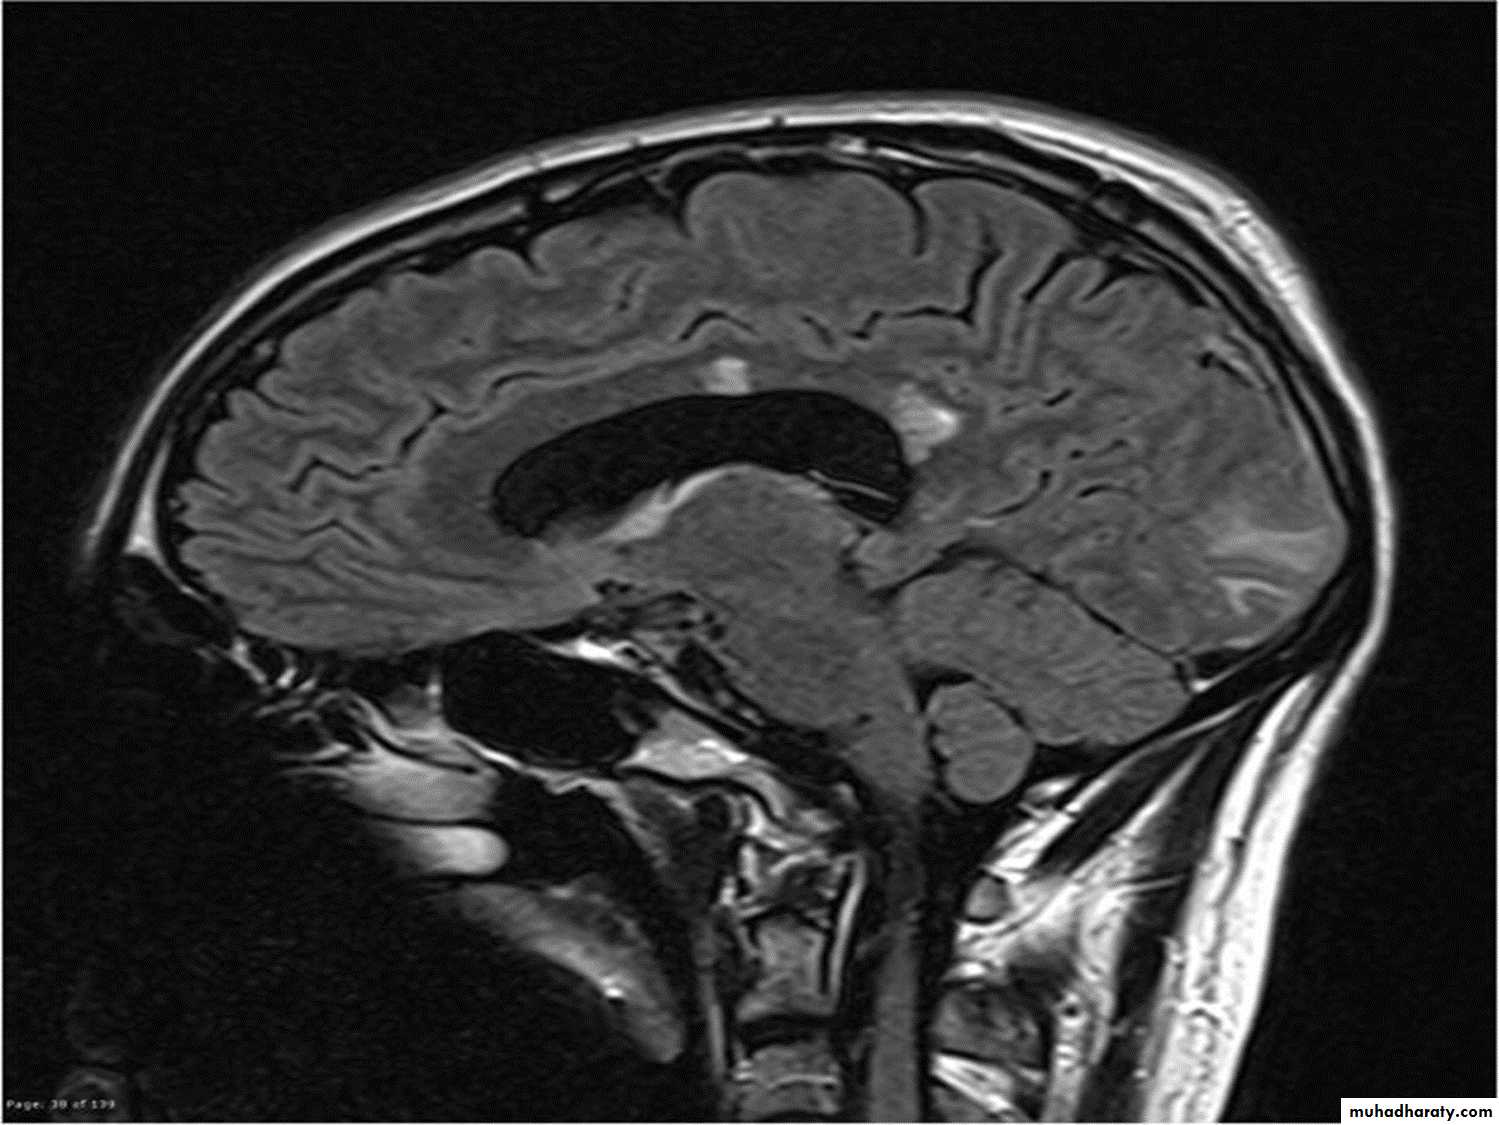

MRI :characteristic abnormalities are found in >95% of patients, although more than 90% of the lesions visualized by MRI are asymptomatic

Lesions are frequently oriented perpendicular to the ventricular surface,(Dawson’s fingers)

Lesions larger than 6 mm located in the corpus callosum, periventricular white matter, brainstem, cerebellum, or spinal cord are particularly helpful diagnostically